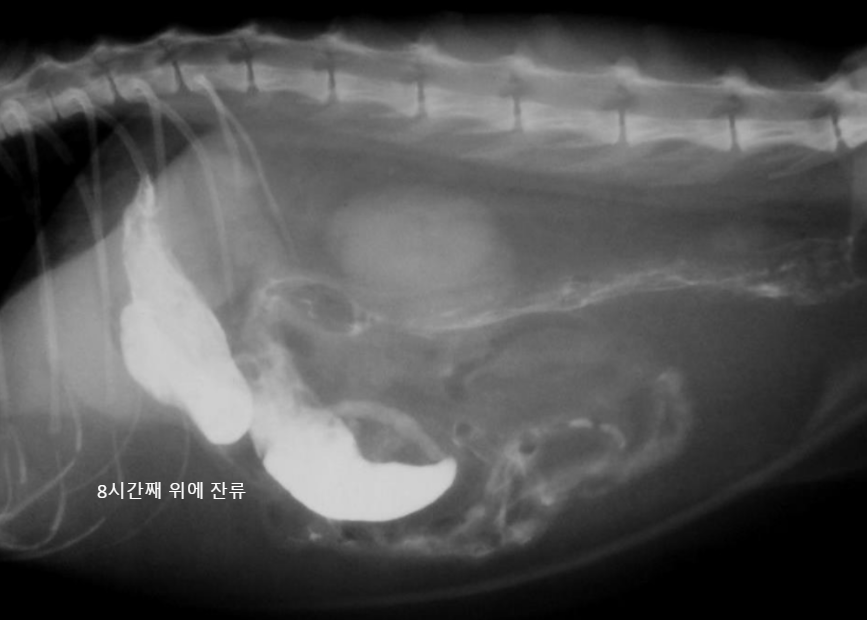

์กฐ์์ ๋ ๊ฐ์์ 1์๊ฐ 20๋ถ~2์๊ฐ, ๊ณ ์์ด์์ 1์๊ฐ ๋ด๋ก ๋ค ๋ฐฐ์ถ๋จ.

- ์ด๋ณด๋ค ์ค๋ ๊ฑธ๋ฆฌ๋ฉด ์์ ๋ฐฐ์ถ์ ๋ฌธ์ ๊ฐ ์๋ ๊ฒ. (๋ฐฐ์ถํ๋ ํ์ด ์ฝํด์ง, ํต๋ก๊ฐ ๋งํ, ์กฐ์์ ํก์ฐฉ/ํก์ ์ด๋ฌผ ์กด์ฌ)

| hairball, ์ฒ, ์ค (๊ณ ์์ด) - ์กฐ์์ ๋ฐฐ์ถ์ด ๋งค์ฐ ๋๋ฆผ (1์๊ฐ์ด๋ฉด ๋๊ฐ์ผ ํ๋๋ฐ, ๋ง 8์๊ฐ..) โ์ ๋จน๊ณ ์ ๋ ธ๋๋ฐ ๊ฐํ์ ์ผ๋ก ๊ตฌํ ํ๋ค โ โ ํค์ด๋ณผ ์์ฌ |

![]() |